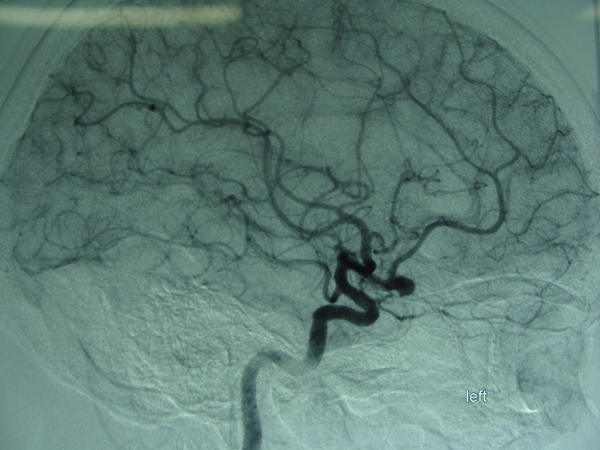

术前DSA侧位